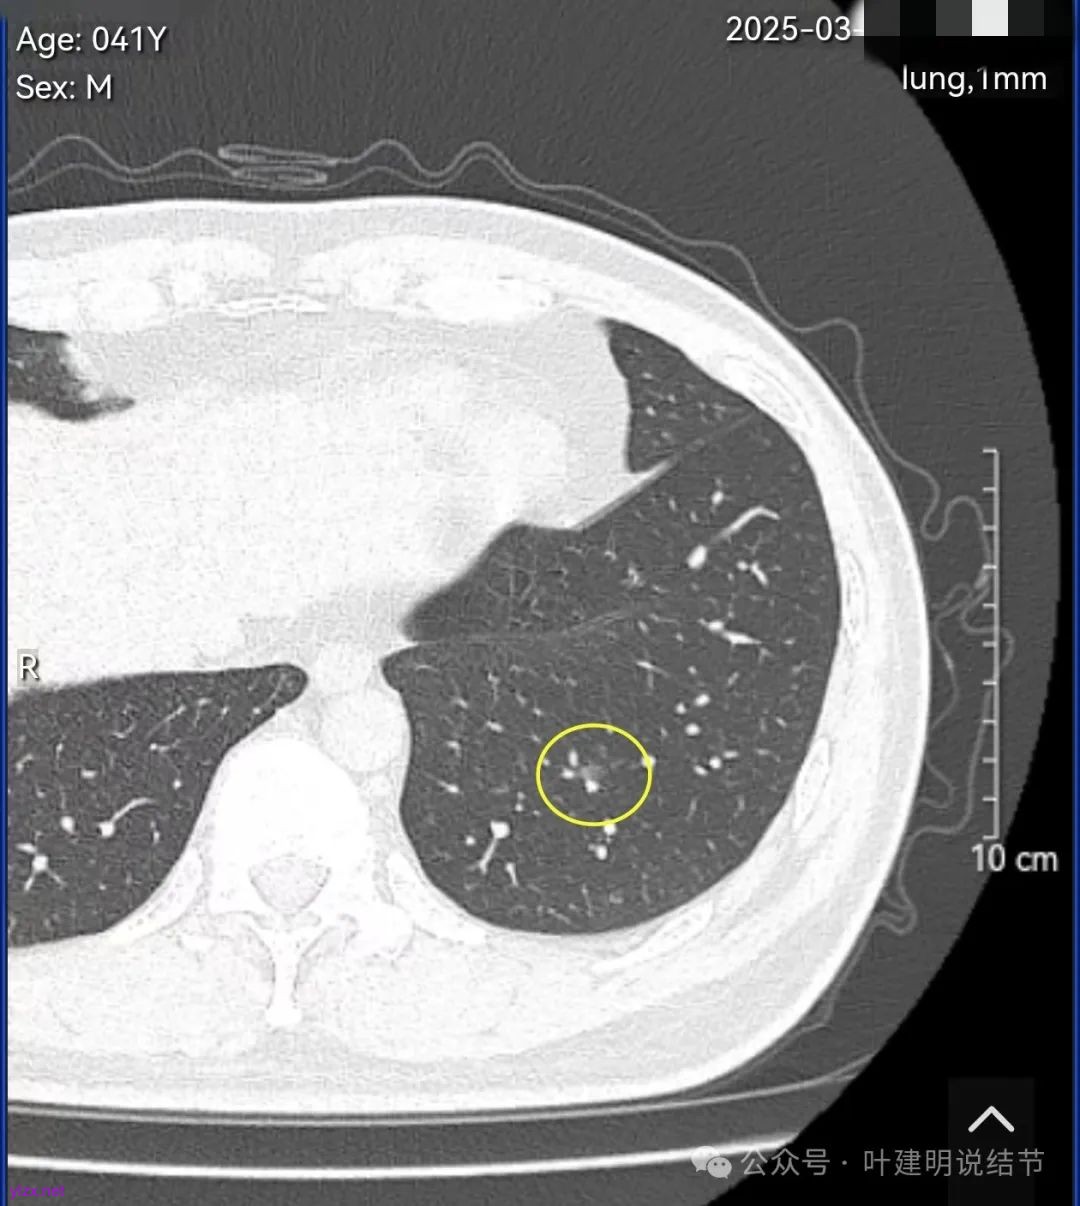

结友男性,41岁,具体病史记不得了,下面是请他重新发我的术前CT报告中截图的影像。

左下叶基底段淡磨玻璃结节,轮廓与边界清楚,考虑肺泡上皮增生可能性大。